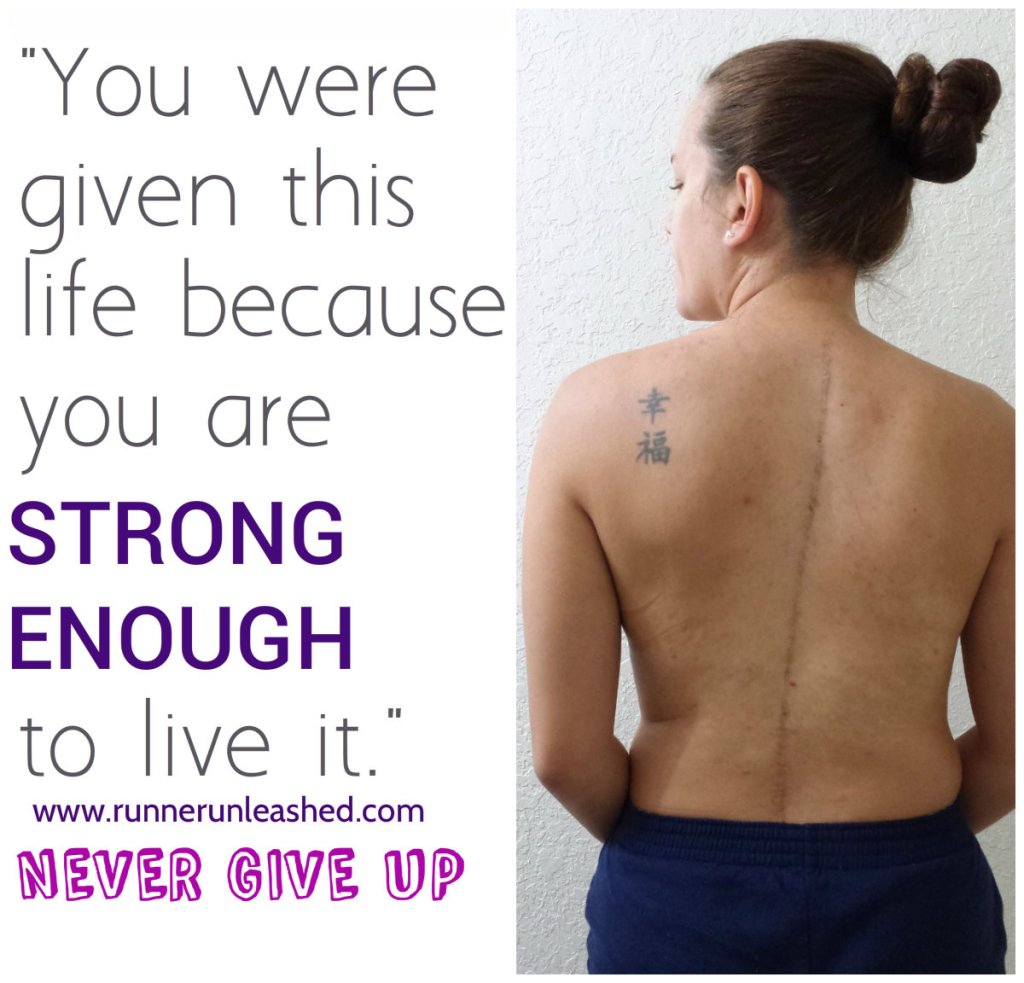

I’ve spent lots of time in hospital beds, physical therapy offices, and on the operating table. Mistakes, accidents, and trauma have left me with chronic back pain and chronic headaches from my Scoliosis. My spine is still very curved, as you can see in the photo, my left side sticks out, and I have a little dimple of space in the bottom. My right shoulder is a lot lower and makes many normal positions such as standing uncomfortable. On top of it, I have severe muscles damage, since to get to my spine they had to cut through the muscles. I actually have no feeling in my right shoulder =( It’s very painful and it’s always present and swollen as shown.

I am a fighter. I deal with a lot on a daily base but I fight through it. I have my bad days, but most of the time I deal with it with a smile on my face. Life is too short to live unhappy and using pain as an excuse. I am using what I have left to make my dreams come true. By doing so, many of my dreams have turned into reality. I am so grateful to have shared my most triumphant with those who support me. I am a Scoliosis warrior and I will fight til the end! Don’t live your life wishing for things to happen, make them happen! The beginning is always the hardest part of the journey. Having enough faith, belief, and desire to reach your goal is enough get you there. Don’t give excuses, if I can get up and do it, so can YOU!